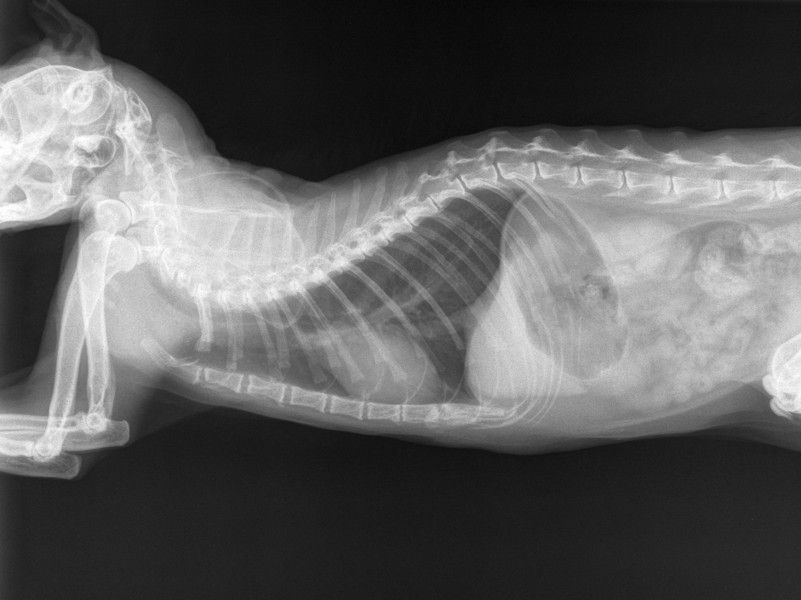

La radiografía es un medio diagnóstico imagenológico que permite, a través de los rayos x, “ver” partes internas del organismo. Esto ya que los rayos son disparados hacia el cuerpo y dependiendo de la densidad de las partes enfocadas, los rayos llegan o no a una placa radiográfica generando una imagen que, hoy en día, se puede obtener digitalmente. Es conocido que este medio es comúnmente utilizado en situaciones relacionadas con problemas óseos, sin embargo el médico veterinario de tu mascota puede recomendar la realización de este examen en diversas situaciones. A continuación te damos un vistazo de la utilidad de la radiografía y la situaciones en que se puede requerir.

Es el medio de más fácil acceso que nos permite evaluar desde pequeñas fisuras y algunos problemas en la columna hasta fracturas complejas. La radiografía permite no sólo diagnosticar estos problemas, sino que es una guía totalmente necesaria en el tratamiento que se debe implementar, sobre todo si se trata de un procedimiento quirúrgico, donde la radiografía es el “mapa” que debe usar el cirujano para manejar los huesos y mantenerlos en la posición adecuada.

Dependiendo del material del cual sea el objeto que haya ingerido una mascota, será posible apreciar su forma, por ejemplo, un objeto de metal será totalmente claro en una placa radiográfica. Por otro lado, cuando se trata de otro tipo de objetos radiolúcidos (que no generan “color blanco” en la placa) como lo son telas o caucho, el uso de medios de contraste es bastante útil. Lo anterior consiste en la administración de una sustancia que genera radiopacidad (genera “color blanco” en la placa) y al entrar al sistema digestivo muestra el trayecto claramente, por lo cual si hay una obstrucción, la sustancia se “estancará” en un punto del trayecto y será visible en la placa radiográfica.

Malposición y tamaño anormal de los órganos

Cada órgano posee cierto aspecto específico en una placa radiográfica que puede ser comparado con lo que se considera “normal”. Esto significa que el médico que realiza la lectura de las radiografías va a identificar si un órgano se encuentra en una posición en la que no debería estar o si su tamaño o forma se encuentran alterados, dando así una guía hacia el diagnóstico.Torsiones gástricas, organomegalias (tamaño aumentado de un órgano), hernias diafragmáticas, entre otras anormalidades pueden llegar a ser identificadas.

Presencia de líquido en cavidad abdominal o torácica

Como se mencionó anteriormente, hay materiales que se pueden identificar dependiendo de su radiopacidad, entre estos encontramos que el líquido genera una radiopacidad alta (se ve de color blanco) y si es hallada en cavidad torácica o en el espacio peritoneal, es indicativo de salida de líquido ya sea por edema o sangrado en estos espacios donde no se debería encontrar. A través de estos hallazgos se puede sugerir la presencia de una hemorragia interna, peritonitis, efusión pleural, entre otras, sin embargo se requieren más exámenes para llegar al diagnóstico acertado.